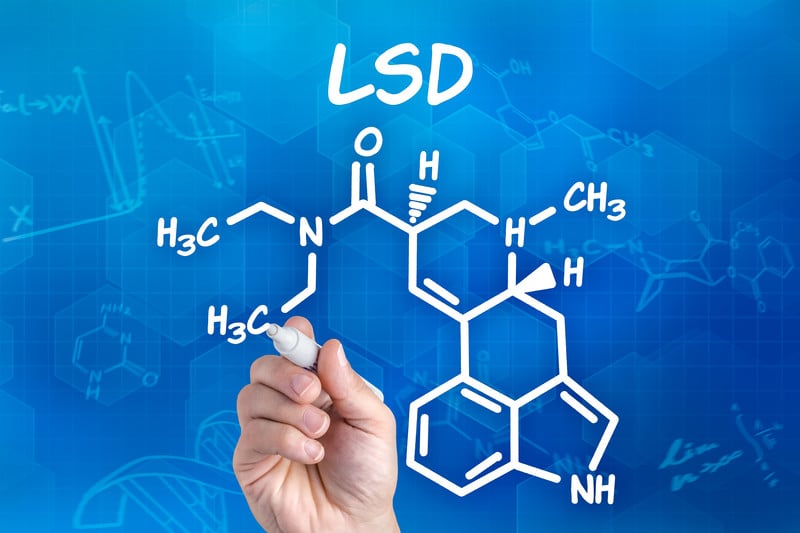

Är lsd beroendeframkallande bör komma efter att du vet vad som är LSD. LSD (D-lysergsyradietylamid) är en av de mest kraftfulla sinnesförändrande kemikalierna. Det är ett klart eller vitt luktfritt material tillverkat av lyserginsyra, som finns i en svamp som växer på råg och andra spannmål. LSD har många andra gatunamn, inklusive acid, blotter acid, dots och mellow yellow. De kariösa kategorierna och taggarna på LSD Drug gör det till en speciell psykedelisk drog.

LSD tas genom munnen. Den har en lätt bitter smak, och finns i tabletter (lsd tabs), kapslar eller som vätska (flytande lsd). Syra säljs vanligtvis på en bit läspapper, och användaren tuggar eller sväljer den för att få i sig läkemedlet. LSD har noll fysiskt beroendepotential. Det är inte fysiskt beroendeframkallande och det är inte en drog som du direkt kommer att vilja göra igen. Detta är inte den typ av läkemedel där en användare upplever abstinens om en annan dos inte intas inom en relativt kort tidsperiod. Men detta svarar inte på frågan om är lsd beroendeframkallande? Ja.

Se vad som gör LSD Drug till en beroendeframkallande pyschedelisk drog.LSD är en sinnesförändrande drog. Man tror att LSD orsakar dess karakteristiska hallucinogena effekter via interaktion med serotoninreceptorerna i hjärnan. Serotonin är en signalsubstans som hjälper till att kontrollera ditt beteende och humör, styr dina sinnen och dämpar dina tankar.